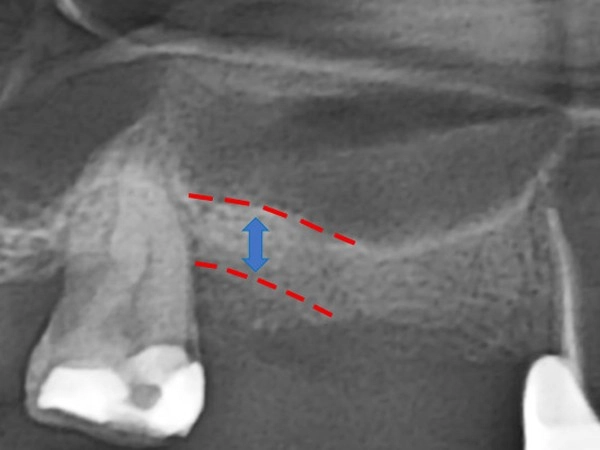

治療後

由於鼻竇空間過大或上顎骨頭萎縮,導致骨頭高度不足